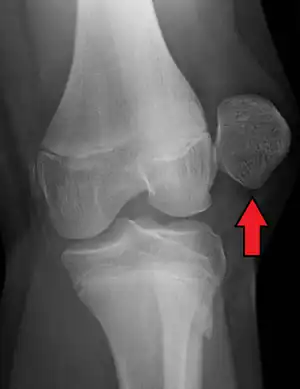

| X-ray showing a patellar dislocation, with the patella out to the side. | |

A patellar dislocation is a knee injury in which the patella (kneecap) slips out of its normal position.[5] Often the knee is partly bent, painful and swollen.[1][2] The patella is also often felt and seen out of place.[1] Complications may include a patella fracture or arthritis.[3]

A patellar dislocation typically occurs when the knee is straight and the lower leg is bent outwards when twisting.[1][2] Occasionally it occurs when the knee is bent and the patella is hit.[1] Commonly associated sports include soccer, gymnastics, and ice hockey.[2] Dislocations nearly always occur away from the midline.[2] Diagnosis is typically based on symptoms and supported by X-rays.[2]